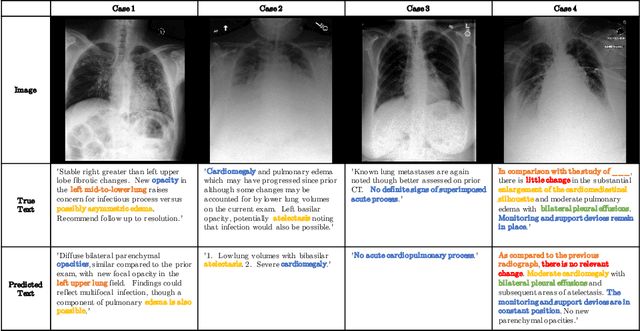

Abstract:Chest radiographs are one of the most common diagnostic modalities in clinical routine. It can be done cheaply, requires minimal equipment, and the image can be diagnosed by every radiologists. However, the number of chest radiographs obtained on a daily basis can easily overwhelm the available clinical capacities. We propose RATCHET: RAdiological Text Captioning for Human Examined Thoraces. RATCHET is a CNN-RNN-based medical transformer that is trained end-to-end. It is capable of extracting image features from chest radiographs, and generates medically accurate text reports that fit seamlessly into clinical work flows. The model is evaluated for its natural language generation ability using common metrics from NLP literature, as well as its medically accuracy through a surrogate report classification task. The model is available for download at: http://www.github.com/farrell236/RATCHET.